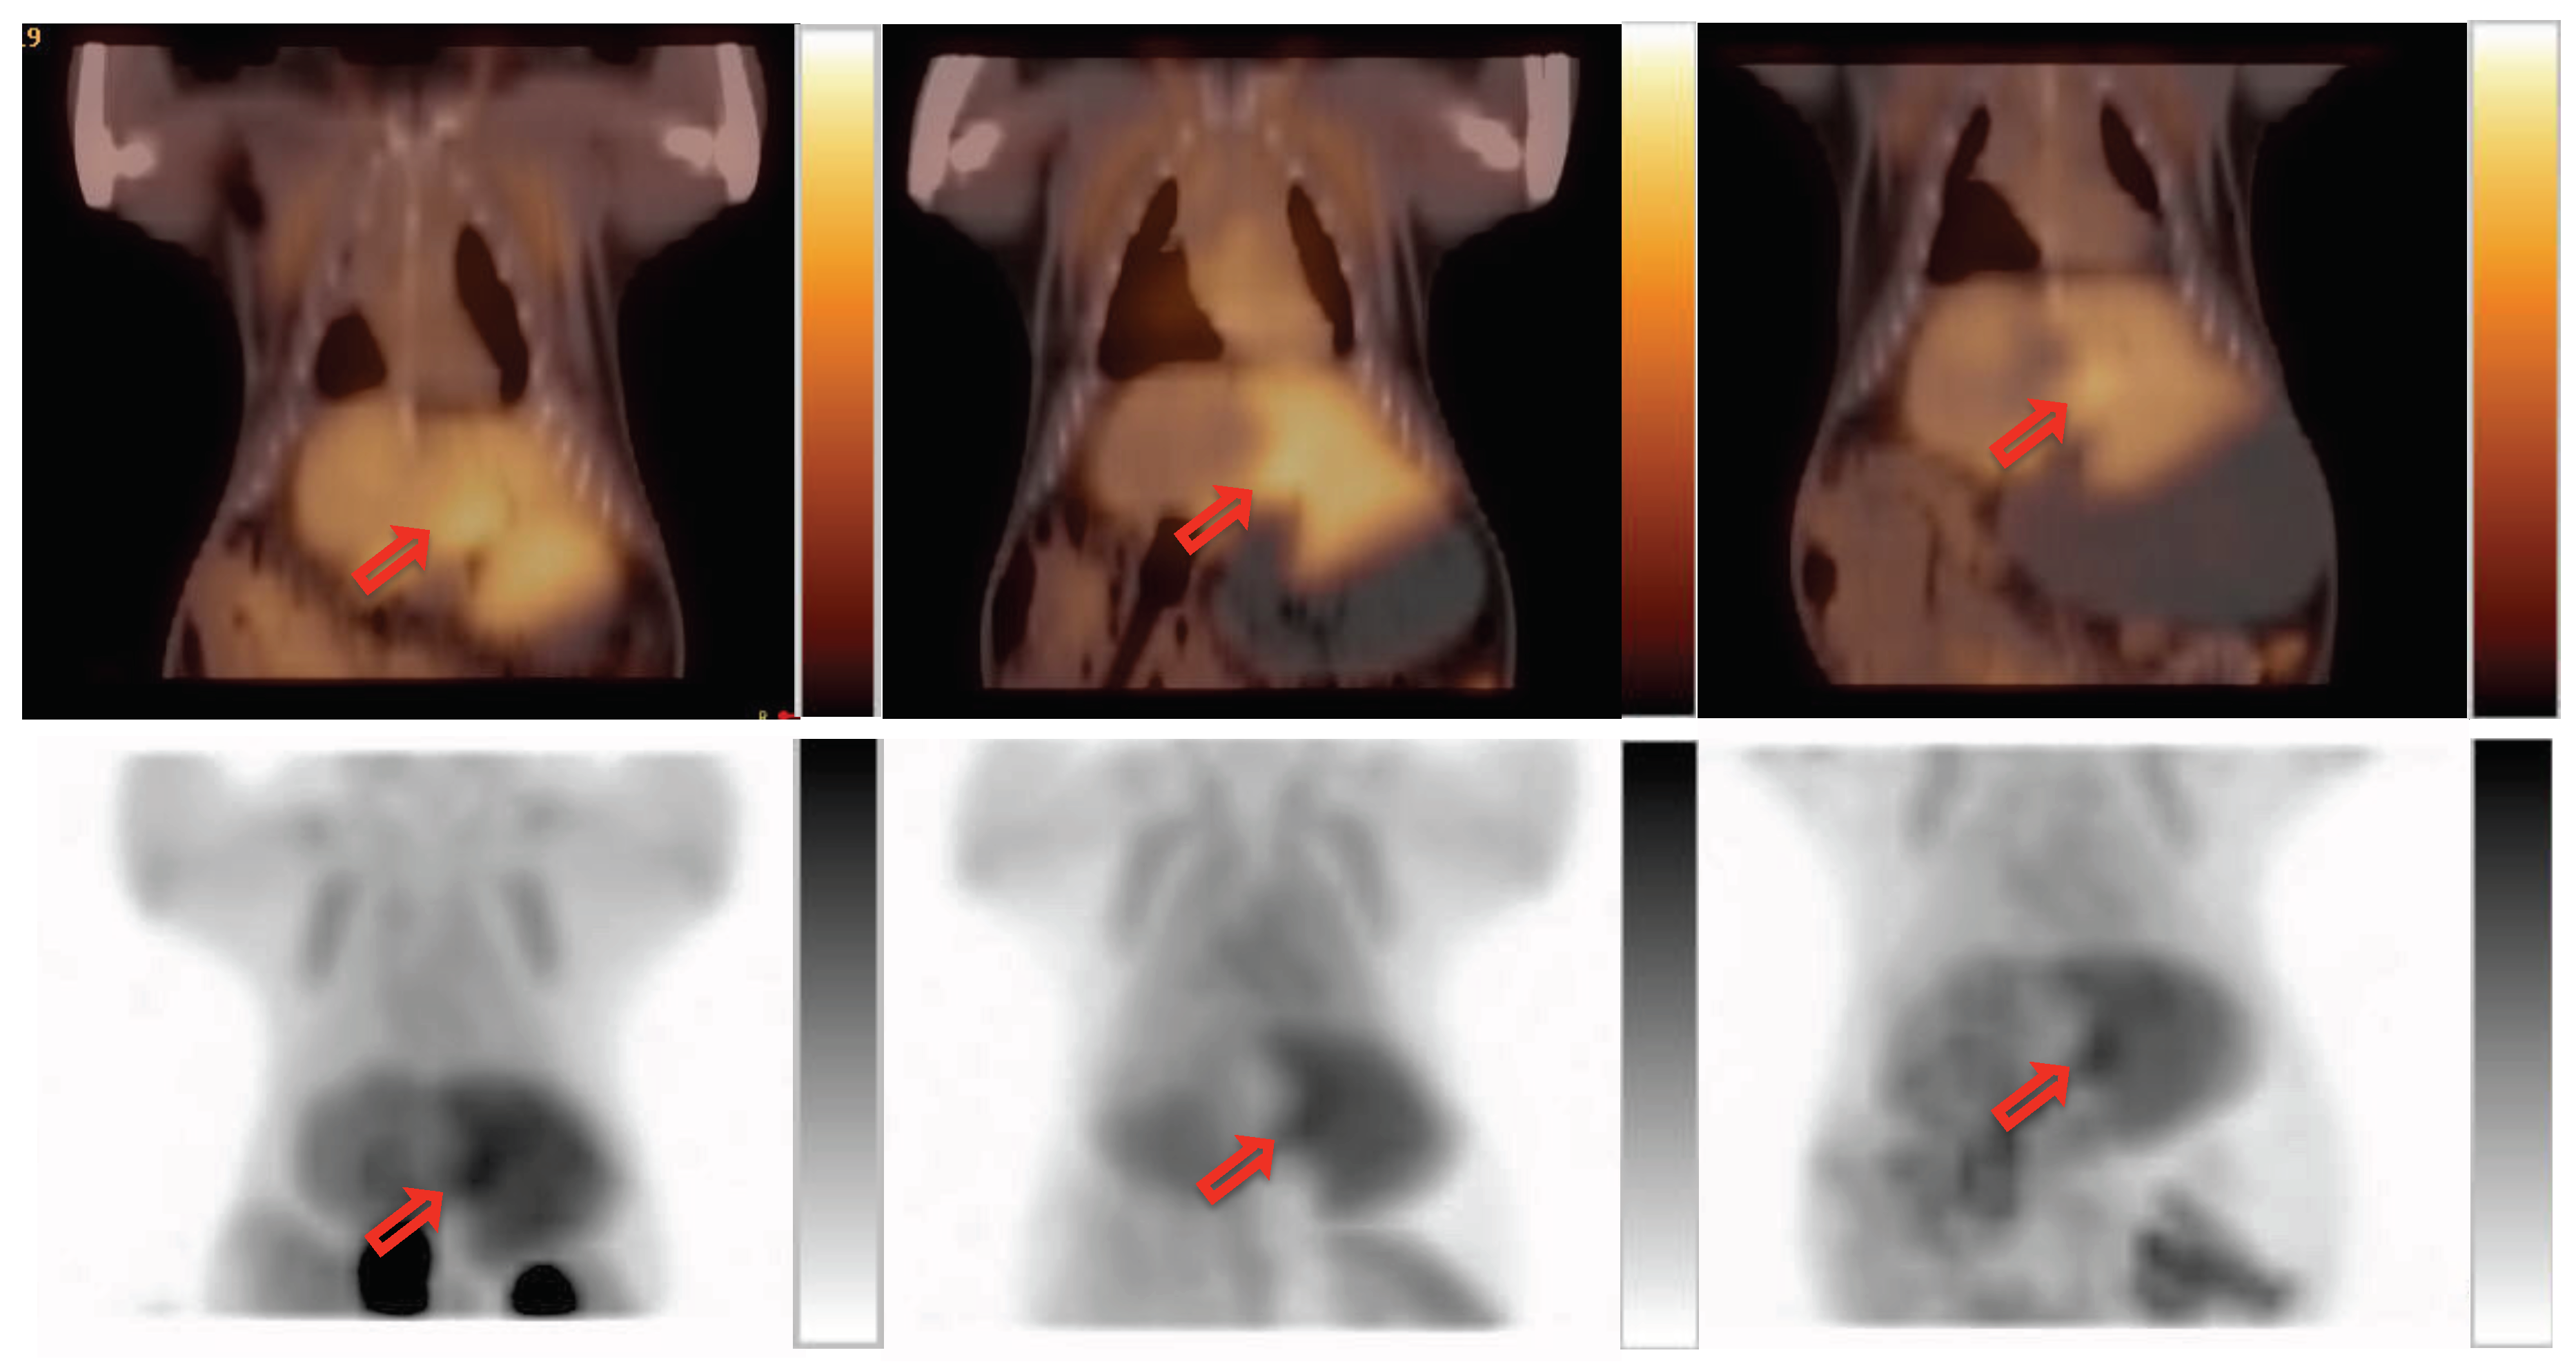

2. Results

2.2. PET Imaging

2.3. Validation